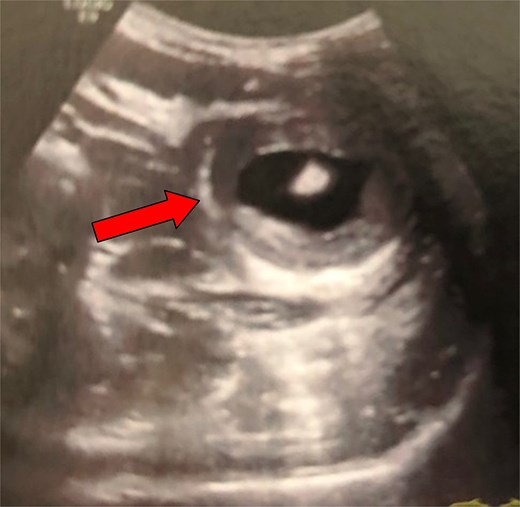

The second case involved a 38-year-old woman with no prior medical history who presented to the emergency department with progressive, recurrent epigastric pain, vomiting, and diarrhea over the past ten days. Physical examination revealed tenderness and a palpable mass in the upper abdomen. All laboratory inflammation markers were within normal limits (WBC: 8.8 mm3/μl, CRP: 0.0 mg/dl). An ultrasound was initially performed, revealing a suspected bowel intussusception based on the characteristic “target sign” (Fig. 2).

Ultrasound examination of the patient (second case) on admission. The typical ‘target sign’ (arrow) is clearly demonstrated, raising the suspicion of a bowel intussusception.

Ultrasound is a noninvasive, radiation-free technique; therefore, it is considered the preferred imaging modality for diagnosing intussusception in children and may also be diagnostic in adult patients. The characteristic ‘target or bull's eye sign’ seen from the intussuscepted loops forming an external ring around the intussusceptum can be depicted by an experienced radiologist [17] (Fig. 2). In paediatric patients, the reported sensitivity of this method is nearly 100%. However, in adult patients, it is significantly lower (30%–60%) [6, 7, 18]. According to Wang et al., if a palpable mass is present, the method's diagnostic accuracy improves considerably, reaching 91% [7]. Of the three cases we present, ultrasound was performed in two patients with epigastric pain to rule out gallbladder issues. It was diagnostic only in the second case, which also had a palpable mass. Regarding CT scan, it seems to be the most useful diagnostic tool in adult intussusception, with reported accuracy ranging from 78% to 100% [6, 7, 12, 18, 19]. Intussusception appears as an inhomogeneous mass with a central fatty area and enhanced blood vessels (representing the intussuscepted mesentery), along with multiple, eccentric layers indicating thickened segments of bowel (the intussusceptum and intussuscipiens) [20]. Additionally, CT can offer indirect clues in malignancy cases (such as metastatic liver lesions or lymphadenopathy). However, in most cases, it cannot identify the primary tumor causing the intussusception.